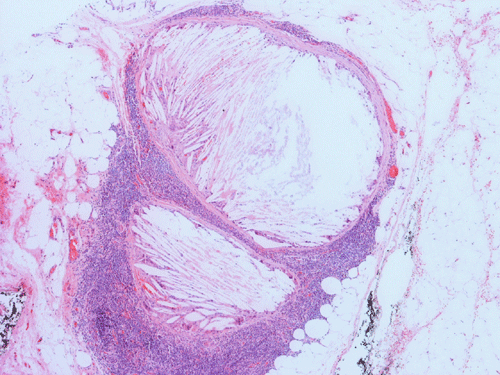

Histopathology: The lesion is encapulated cystic structure with the wall lined by nodules of lymphoid tissue (Panel A  and B) that are devoid of any evidence of hematopoiecic malignancy. Within this lymphoid tissue are small pink islands (Arrow in Panel C) and on higher magnification (Panel D) these islands are squamous cell nests. These islands are Hassell corpuscles and the lymphoid tissue is in fact thymic tissue. The cyst appears to have sustained repeated hemorrages. Both recent hemorrhage (Panel E) and cholesterol clefts consistent with resolved hemorrhage (Panel F) are present.